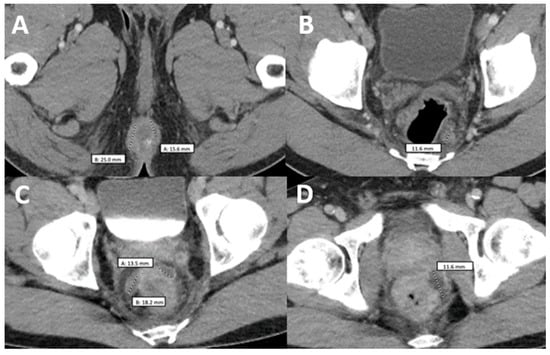

Figure 2.

Comparison of two computerized tomographies of the pelvis with contrast. (A,B) were taken when the patient was already diagnosed with monkeypox but had not taken any medication and showed a rim-enhancing perirectal abscess measuring up to 2.5 cm in AP dimension (A) with a perirectal lymph node measuring up to 12 mm in short axis dimension (B–D) were taken when the patient came back after antiretroviral treatment with worsening of proctitis-related symptoms and showed three persistent vs. new rim-enhancing perirectal abscess.

Two weeks later and 6 weeks after the initial presentation, the patient returned to the ED after 5 days of the worsening of the existing Mpox lesions, bilateral periorbital edema, facial pain, and increasingly severe rectal pain. Of note, this was 15 days after starting ART and after completing the first course of tecovirimat for 14 days. Upon physical exam, he had numerous vesicles and pustules with central umbilication and necrotic crusting on his face (Figure 1C,E). Over his prior active Mpox lesions, he had hyperpigmentation and collarettes of scales, signs of excoriation with surrounding erythema. On his perirectal region, several rounded punched-out erosions with surrounding purulent discharge (Figure 1D). A second course of tecovirimat was initiated due to disease progression in the setting of a prior improvement with tecovirimat. Repeat abdominal/pelvic CT showed multiple perirectal abscesses indicating proctitis of the entire rectosigmoid segment. He underwent testing with urinary gonorrhea and chlamydia PCR, which was positive only for chlamydia. Due to presumptive lymphogranuloma venereum (LGV) proctitis, chlamydia urethritis, and perirectal abscess, the patient was started on oral doxycycline for 21 days as well as oral metronidazole and levofloxacin (Figure 2). At this time, surgical drainage was deferred. After 5 days of hospitalization, the patient’s symptoms improved, and he was discharged on a second 14-day course of tecovirimat, along with his other antimicrobial regimens and prophylaxis.